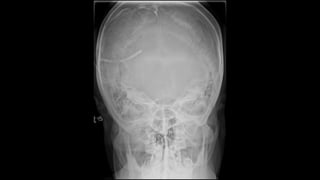

Occipitofrontal view

 This projection is used to demonstrate the frontal and

ethmoidal sinuses.

 It is also known as the Caldwell’s view.

 The patient is seated upright in front of the receptor and their

forehead and nose are placed against it.

 The beam is centred at around 15 to exit at the nasion.

⁰

• collimation

• lateral to the skin margins

• superior and inferior to the borders of the sinus cavities

Two frontal views of the skull demonstrate an incidental rounded, sclerotic lesion growing into the right frontal sinus (white arrows).

z Occipitofrontal view  Thisprojection is used to demonstrate the frontal and ethmoidal sinuses.  It is also known as the Caldwell’s view.  The patient is seated upright in front of the receptor and their forehead and nose are placed against it.  The beam is centred at around 15 to exit at the nasion. ⁰ • collimation • lateral to the skin margins • superior and inferior to the borders of the sinus cavities

Two frontal viewsof the skull demonstrate an incidental rounded, sclerotic lesion growing into the right frontal sinus (white arrows).